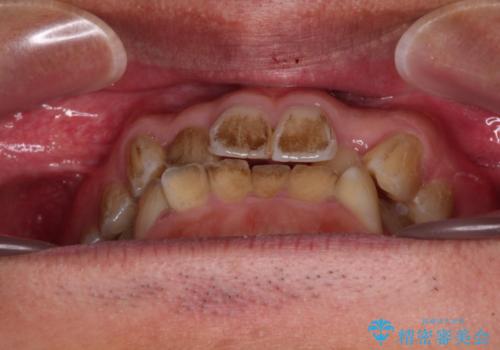

- 前歯のデコボコを気にして来院された患者様です。

極力費用を抑えた上で、自己管理の煩わしの少ない装置を希望とのことで、メタルブラケットによるワイヤー矯正を選択されました。

舌の突出癖があり、デコボコが解消される際に出っ歯傾向になる恐れがあるため、舌のトレーニングを行っていただきながら、矯正治療を進めていくこととしました。